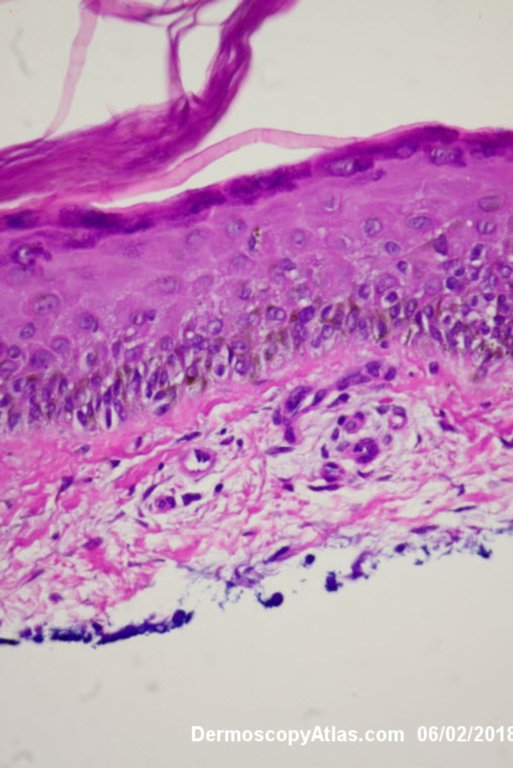

Image Number #3421 (Melanoma invasive)

Site: Leg

Diagnosis: Melanoma invasive

Description: Multiple colours in this pigmented lesion on the lower leg. New pink area

Lady in her early 80s who presented with this lesion on her ankle. The pigmented area had been there for some time but the pink area was bleeding and new. Shave of surrounding area and a punch biopsy of the new pink area showed mainly surrounding in situ melanoma with invasive melanoma in the pink area 1.8 mm thick. Having a 2cms margin excision of the whole area and a graft.